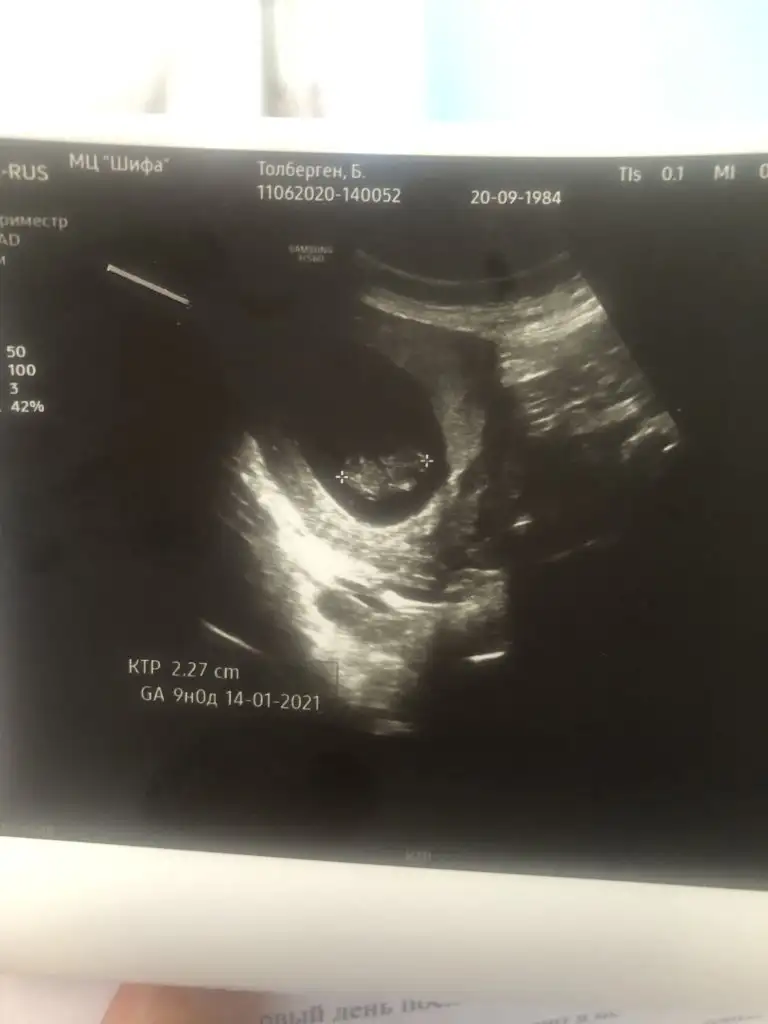

Buna göre kız siz 11 12 13 hafta usg de paylaşınEki Görüntüle 2648636Ikra meyra bakabilir msnz? cinsiyeti cok merak ediyorum bu 5+6 gunluk usg. Bi tahmin olur mu?

5+6 gunluk karindan usg unuttum.Buna göre kız siz 11 12 13 hafta usg de paylaşın